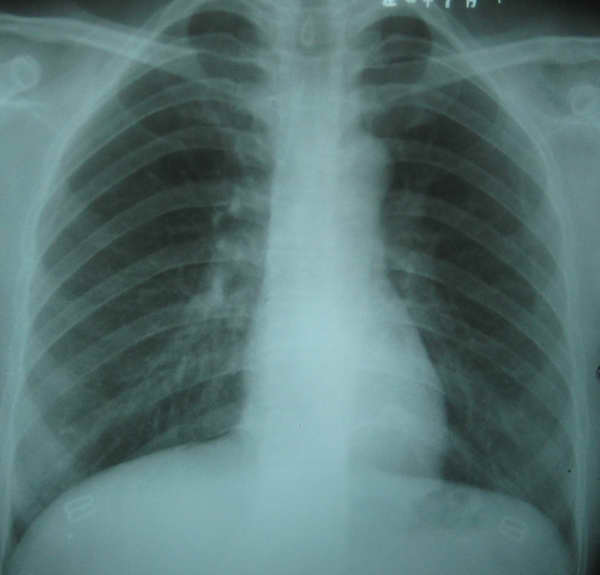

标题: X4477:F,37Y。主诉时有胸闷,双上下肢及眼睑浮肿。心脏听 [打印本页]

1、此病例心胸比率为0.37,心影横径临界9.0cm。

2、小心脏综合征(small heart syndrome)报道诊断标准。(1)x线胸片显示小心脏,心胸比率<0.40,心脏横径均<9.0 cm。

3、请大家继续发表意见。提供小心脏综合症诊断标准资料。

小心脏综合症是指x线片上心影小于正常,心胸比率儿童<0.40,成人<0.42,心脏横径<9-12cm.临床上轻度运动后出现机体供血不足而产生的一系列症状,如心悸、无力、胸前区疼痛、直立时易头晕、恶心、心动过速的一种特殊神经衰弱的症候群,而非心脏器质性病变.但心脏小,患者无任何循环系统症状和体征均不属此症.本例症状不符,应考虑滴状心。水肿的原因,除心脏外,还有肾脏、肝脏病变等其他原因,建议进一步检查。